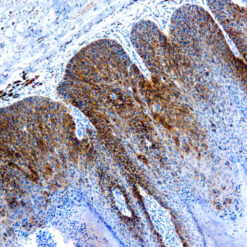

Iba1 (AIF1)

Actin-binding protein that enhances membrane ruffling and RAC activation. Enhances the actin-bundling activity of LCP1. Binds calcium. Plays a role in RAC signaling and in phagocytosis. AIF1 colocalizes with actin, and upon stimulation, translocates to lamellipodia. It is also a marker of human microglia and is expressed by macrophages in injured skeletal muscle. The gene encoding AIF1 resides in the tumor necrosis factor (TNF) cluster of genes, located in the region represented by the human major histocompatibility complex (MHC).

| Positive Control Tissue | Spleen |